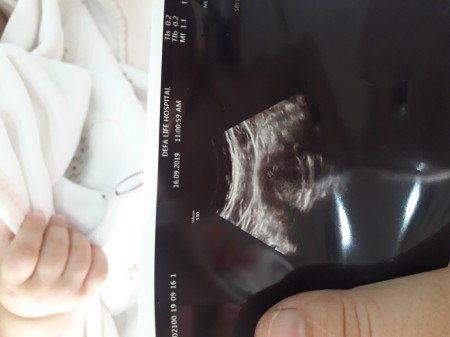

Bu Ultrasonda Bebek Gorebilen Var Mi Kizlarsoruyor

Resimli Ultrason Kese Bos Mu Hamilelik Donemi Genel

Ultrason Fotosu Hamilelik Donemi Genel